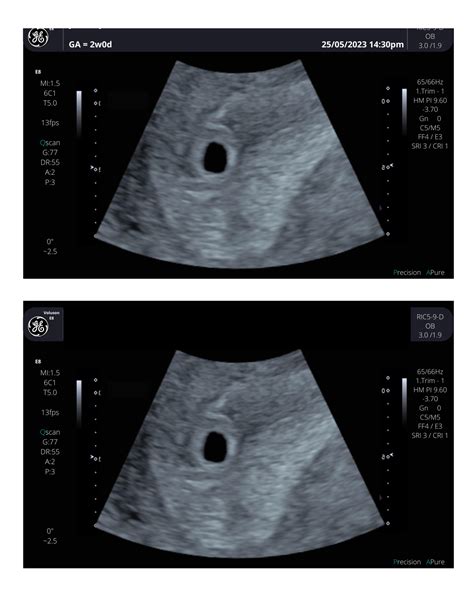

• baby at 4 weeks ultrasound

• baby at 4 weeks pregnant

• baby at 4 weeks gestation